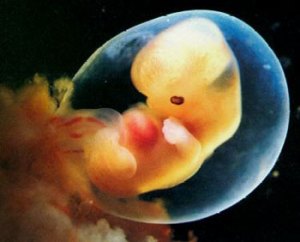

«Le imprese indipendenti di aborto si stanno chiudendo a un ritmo rapido in tutti gli Stati Uniti, mentre gli Stati emanano leggi per proteggere i nascituri e le madri dall'aborto. Un nuovo rapporto della rete pro-aborto Abortion Care ha rilevato che quasi un terzo di tutte le strutture abortive indipendenti ha chiuso dal 2012». Il popolo americano sta aprendo gli occhi di fronte alle menzogne delle campagne abortiste. Ed ecco il risultato.